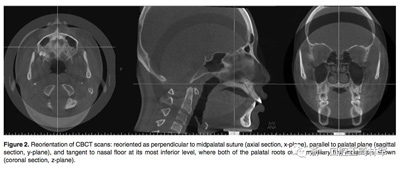

在治療前(T1)和擴(kuò)弓后3個(gè)月(T2)拍攝CBCT,獲得的數(shù)據(jù)由In Vivo Dental(Anatomage,San Jose,Calif)分析。為了在T1和T2階段設(shè)置相同的參考平面,CBCT圖像沿著腭中縫(x平面)定向,平行于腭平面(y平面)并且與鼻底(z平面)相切(Figure 2)。在腭中縫處評估橫向骨骼擴(kuò)張,并在三個(gè)不同的平面進(jìn)行線性測量:鼻底,硬腭和硬腭以下5mm。在根尖和牙冠水平測量橫向牙齒擴(kuò)張(Figure 3)。評估兩側(cè)的牙槽傾斜度,牙長軸,牙齒垂直高度和骨開裂等情況(Figure 4,5)。所有測量均在每個(gè)上頜前磨牙和磨牙區(qū)域進(jìn)行。